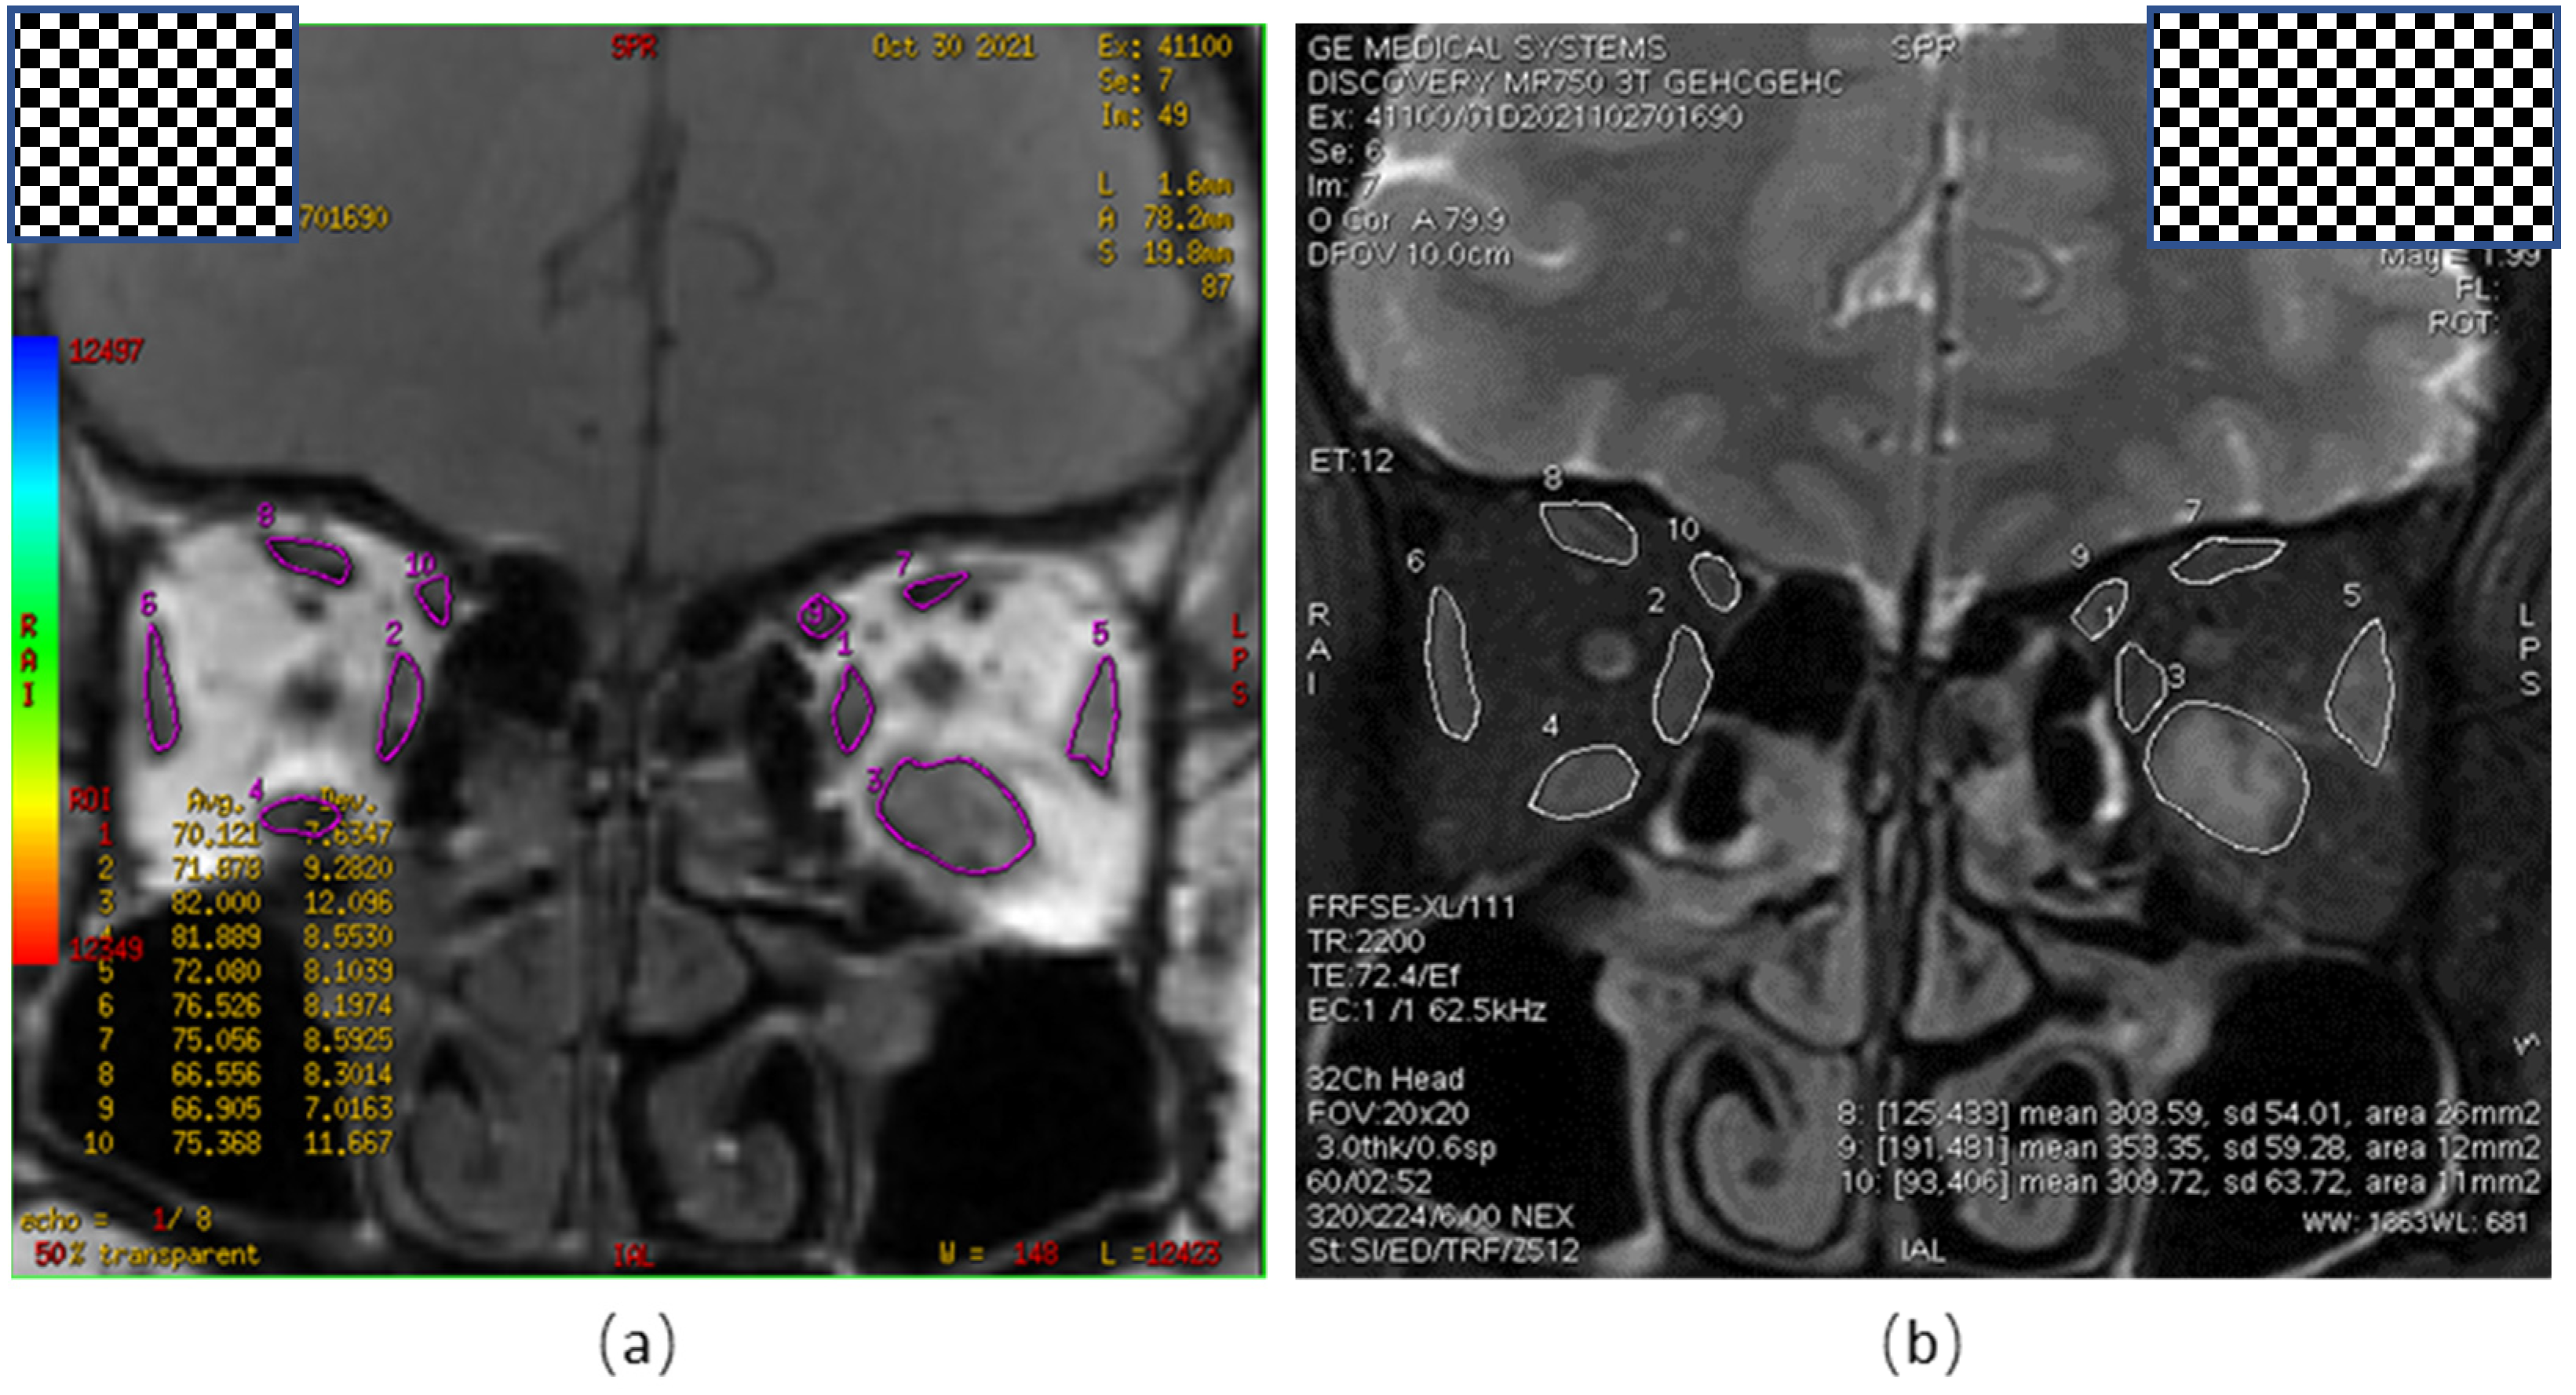

2.2. Measurement of Orbital MRI-T2 Mapping Parameters

2.3. Image Analysis